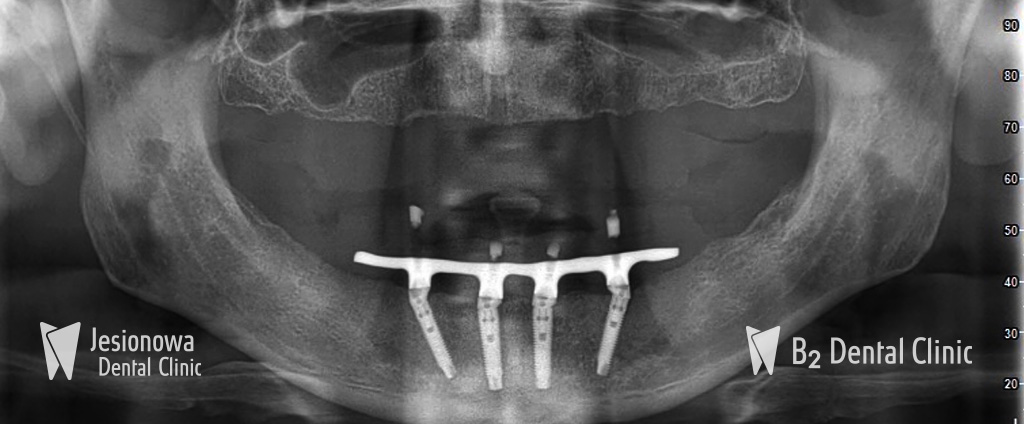

All on 4